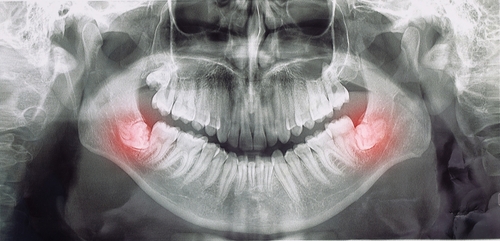

이런 방향은 촬영을 해보면 쉽게

확인할 수 있고,

조기 발치를 고려하는 데

도움이 됩니다.

사랑니 위치와 방향은 사람마다

크게 다르기 때문에 정기적인

촬영이 매우 중요합니다.

특히 아래턱 사랑니는 신경과

가까운 자리에 자리 잡는 경우가 있어,

발치를 결정할 때 뿌리와 신경의

거리·각도·깊이 등을 꼼꼼히

확인하게 됩니다.